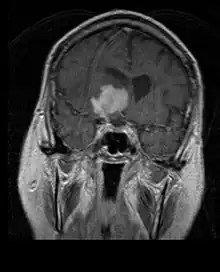

A tomografia computadorizada (TC) e a ressonância magnética (RM) podem detectar efetivamente uma neoplasia no cérebro. A RM é mais sensível que a TC para identificar lesões, mas contraindicações para pacientes com marcapasso cardíaco, próteses incompatíveis, clipes metálicos e outros. A TC continua sendo o método de escolha para detectar calcificações dentro de lesões ou erosões ósseas da calota craniana ou da base. A utilização de agentes de contraste, que são iodados no caso da TC e paramagnéticos ( gadolínio ) no caso da RM, permite a aquisição de informações sobre a vascularização e integridade da barreira hematoencefálica, uma melhor definição do tumor tumoral comparado ao edema circundante e à geração de hipóteses sobre o grau de malignidade . O exame radiológico também permite avaliar os efeitos mecânicos e consequentes alterações nas estruturas cerebrais decorrentes do tumor, como hidrocefalia e hérnias, cujos efeitos podem ser fatais. Finalmente, na preparação para a cirurgia, esse diagnóstico pode ser usado para determinar a localização da lesão ou a infiltração do tumor em áreas vitais do cérebro. Para isso, a RM é mais eficiente que a TC, pois pode fornecer imagens tridimensionais.

As ferramentas de diagnóstico por imagem radiológica destacam a mudança no tecido neoplásico em comparação com o parênquima cerebral normal (através de alterações na densidade do tecido fotografado eletronicamente na TC e na intensidade do sinal na RM). Como a maioria dos tecidos patológicos, os tumores também são reconhecidos por um acúmulo aumentado de água intracelular. Na tomografia computadorizada aparecem hipodensa, ou seja, de menor densidade que o parênquima cerebral, na tomografia de ressonância magnética nuclear com relaxamento spin-lattice T 1 hipointenso e em relaxamento spin-spin T 2 bem como a ponderação de prótons (PD) hiperintensa.

A área saudável do cérebro não deve mostrar nenhuma luminescência específica em uma imagem radiológica. Portanto, nem é preciso dizer que é dada atenção a faixas de sinal de contraste maiores.

No tecido tumoral, em geral, a maior proporção de realce pelo contraste se deve à barreira hemato-tumor particular que permite a passagem de iodo (TC) e gadolínio (RM) para o espaço intersticial extravascular intratumoral. Isso aumenta o sinal (densidade ou intensidade) do tumor. No entanto, deve-se ter cuidado para garantir que o realce do contraste não diferencie definitivamente a neoplasia do edema periferida. De fato, o achado anátomo-patológico no tecido tumoral de glioma infiltrante maligno, como no glioblastoma e no astrocitoma anaplásico, também mostra além do edema vasogênico causado pela destruição da barreira hematoencefálica pelo tumor. Esta última condição clínica é pouco detectável pelo diagnóstico por imagem.

A tomografia computadorizada do cérebro normalmente mostra uma massa de tecido que pode ser realçada por qualquer contraste. Na TC, os gliomas de baixo grau geralmente parecem isodensos ao parênquima normal e, portanto, podem não apresentar realce pelo contraste. Da mesma forma, lesões na fossa posterior do crânio são difíceis de identificar na TC. Consequentemente, os resultados dessa tomografia isoladamente nem sempre são suficientes para fins diagnósticos. Em casos duvidosos, o uso da ressonância magnética mais sensível é essencial.

Na ressonância magnética, um tumor intracraniano aparece como uma lesão maciça que pode se tornar mais luminescente após o uso do agente de contraste. No entanto, há sempre uma anomalia de sinal na ressonância magnética, que indica a presença de neoplasia ou edema vasogênico. Normalmente, o aumento da luminescência (realce pelo contraste) é indicativo de um tumor de grau mais alto de malignidade. Um anel contrastante é característico do glioblastoma, com a porção luminescente correspondendo à parte vital do tumor maligno e a área mais escura-hipointense à necrose tecidual.